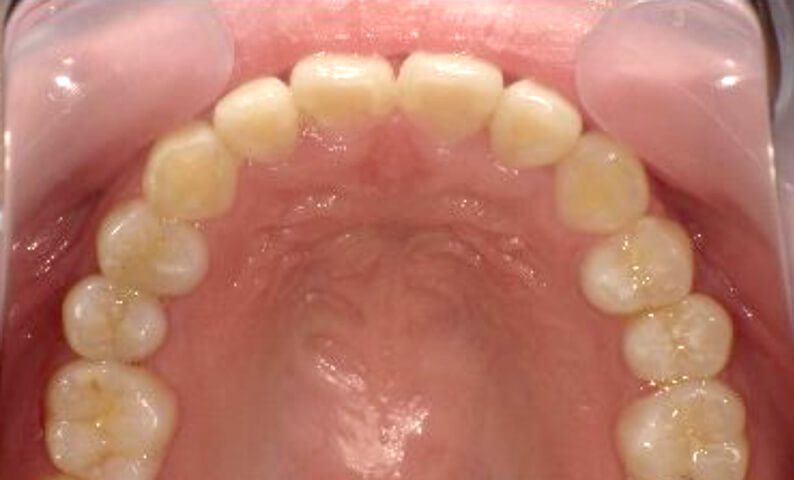

症例_018 上顎だけの部分矯正

治療期間:7ヶ月金額:30万円+税女性前歯のガタガタ上の前歯だけ

| Before | After |

|---|---|

|